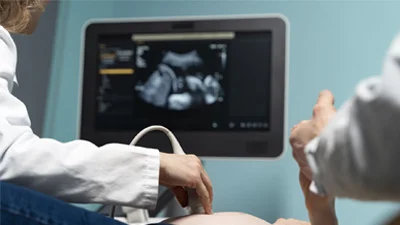

A safe and painless non-invasive procedure using sound waves to visualize soft tissues, organs, and blood flow.